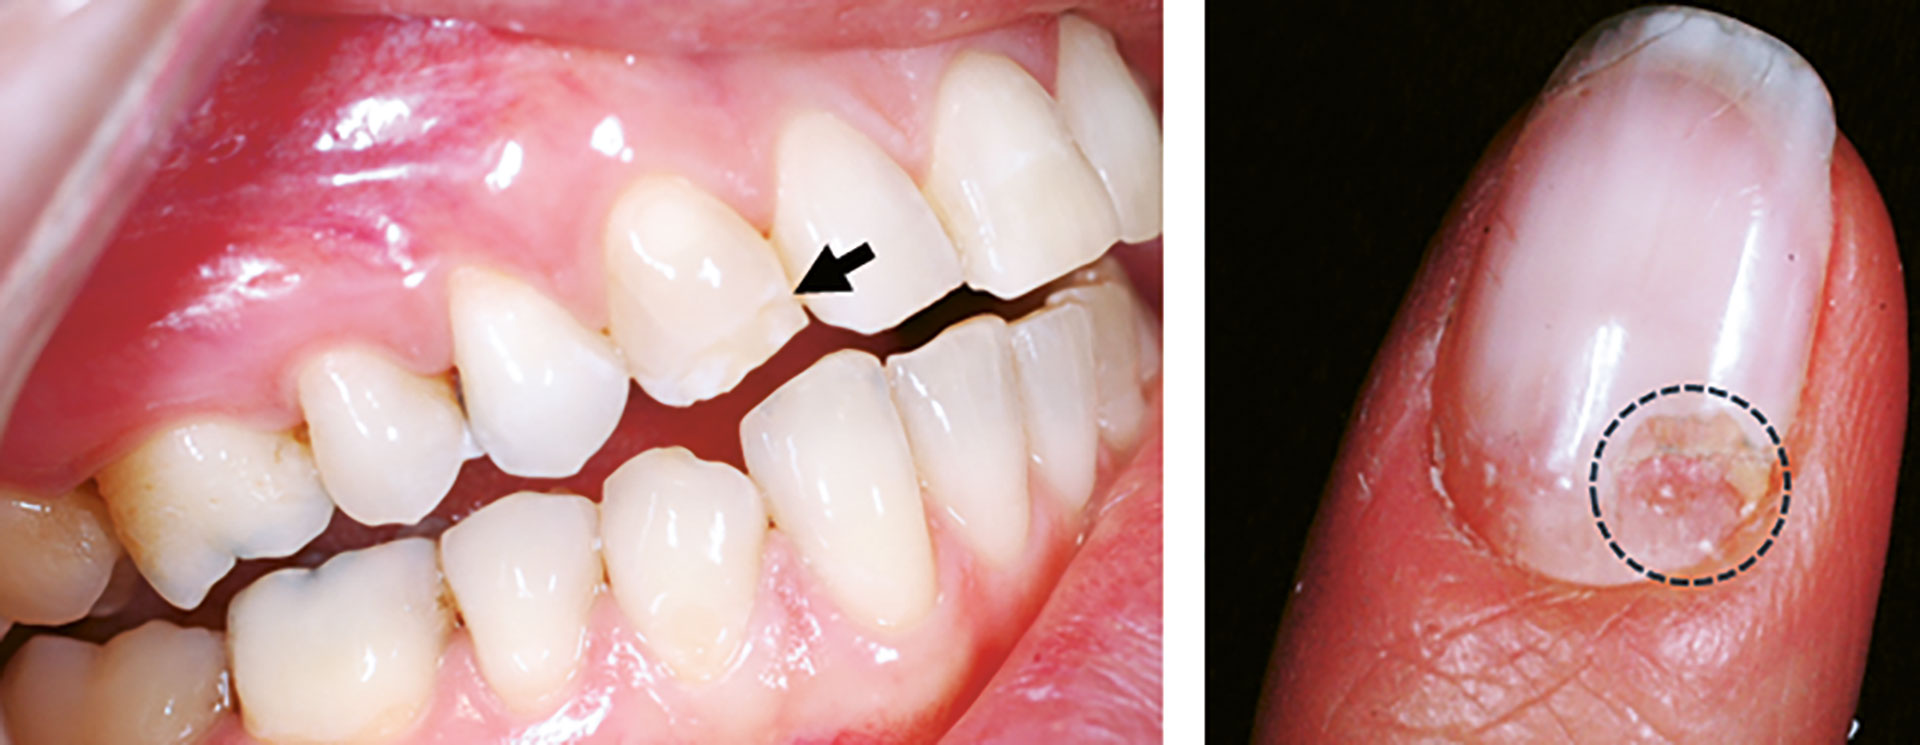

Figur 4

Figur 4. Intraoralt foto av hypomineralisert emalje (pil) og klinisk foto av negl med negldystrofi (stiplet område). Denne pasienten har få orale manifestasjoner av APS-1, men kan her sees på tann 13 med hypomineralisert emalje (pil). Pasienten har i tillegg forandringer på negl med groper og avskalling som er forenelig med APS-1. Forandringen ble først diagnostisert som soppinfeksjon før det ble rediagnostisert som negldystrofi (stiplet sirkel).

Pasienten ble diagnostisert med Addisons sykdom i en alder av 23 år. Samme år ble pasienten diagnostisert med soppinfeksjon på negl som senere ble kategorisert som negledystrofi (figur 4). Pasienten hadde en kjent arvelig predisposisjon ettersom ett av søsknene allerede var diagnostisert med APS-1, og pasienten fikk også påvist kronisk oral candidainfeksjon. AIRE-mutasjoner ble påvist i begge alleler. Hen hadde flere ulike autoantistoffer som er vanlige ved ulike komponenter ved APS-1-syndromet (21OH- og 17OH-autoantistoffer som korreleres med binyrebarksvikt, og NALP5-rettede antistoffer som er vanlig ved hypoparatyreoidisme). I tillegg fant man autoantistoffer mot IFN-omega.

Intraoral undersøkelse: Pasienten har kun påvisbare defekter på 11, 13, 31. Tann 11 var restaurert med kompositt på grunn av emaljedefekt incisalt og bukkalt. Ingen periodontal sykdom eller aktive kariesangrep ble registrert. Ustimulert og stimulert salivamåling ble utført med normale funn. Slimhinneprøve for Candida albicans viste ingen vekst.